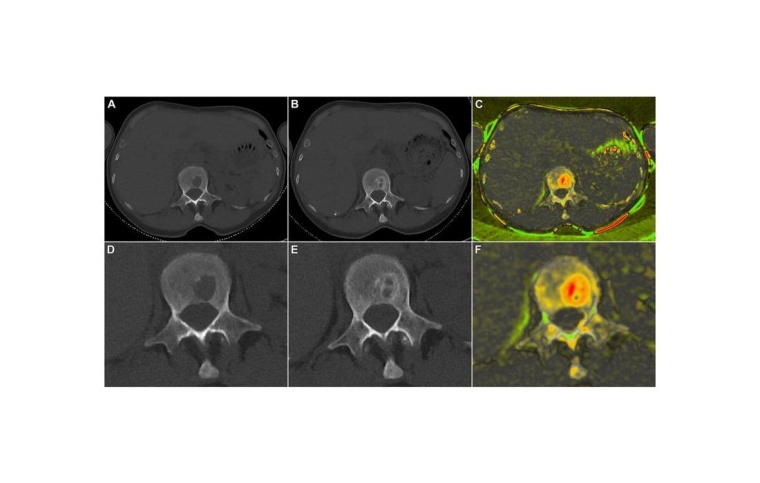

Am Uniklinikum Würzburg haben die Radiologen Dr. Jan Peter Grunz und Privatdozent Dr. Andreas Kunz unabhängig voneinander Röntgenbilder beurteilt, die von insgesamt 20 Patientinnen und Patienten mit einem neu diagnostizierten Multiplen Myelom vor und nach der standardisierten E-KRd-Therapie mittels Computertomografie erstellt wurden. „Die erste Herausforderung war das Finden und Messen der Läsionen zu beiden Zeitpunkten“, kommentiert Jan-Peter Grunz, der die Ergebnisse als Erstautor im Fachjournal Cancers publiziert hat. Insgesamt sind den Radiologen 108 Läsionen aufgefallen, wovon 94 von beiden entdeckt wurden, 14 nur von jeweils einem.

„Unterm Strich haben wir in der Studie gezeigt, dass wir die Läsionen mit einer Standardabweichung von 1,2 Millimetern verlässlich erfassen und messen können“, resümiert Jan-Peter Grunz. Gemeinsam mit dem Bioinformatiker Dr. Dirk Hasenclever aus Leipzig haben die Radiologen aber nicht nur ein quantifizierbares Maß geliefert, welches man auf andere Studien übertragen kann, sondern auch den Remineralisierungsprozess qualitativ dargestellt. „Mit einer speziellen Farbkodierung konnten wir die Regeneration im inneren und äußeren Bereich der Knochen sichtbar machen“, erläutert Jan-Peter Grunz.